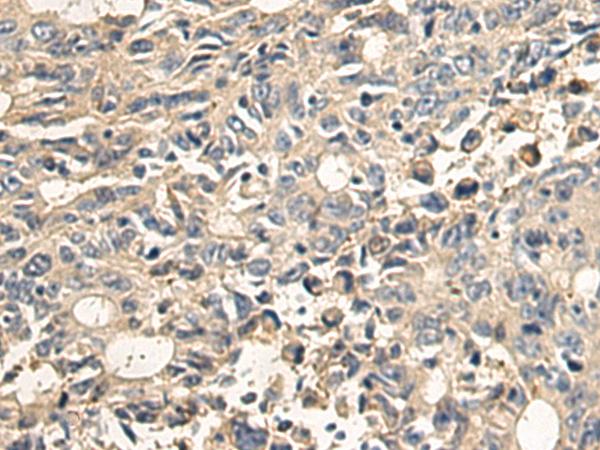

IHC positive control: |

Human lung cancer and Human liver cancer; Human colorectal cancer and Human esophagus cancer |

IHC Recommend dilution: |

100-500 |